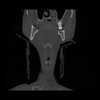

13 P.BLANDAS,,Coronal,2.000,P.BLANDAS,Coronal,